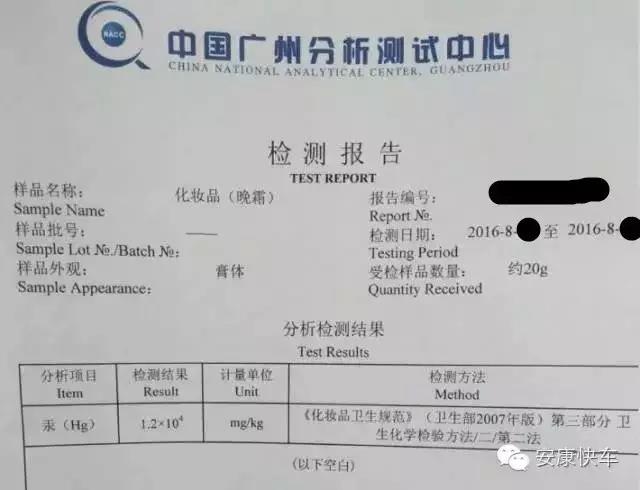

西西的故事(一)——化妆品有毒,你们还敢用吗?

西西的故事(一)——化妆品有毒,你们还敢用吗?

发布日期:2016-10-12 点击:429

摘要: 化妆品有毒,你知道吗?一女子因购买三无化妆品,汞含量严重超标,导致汞中毒,令人扼腕叹息。本文介绍汞的接触途径、危害,汞中......